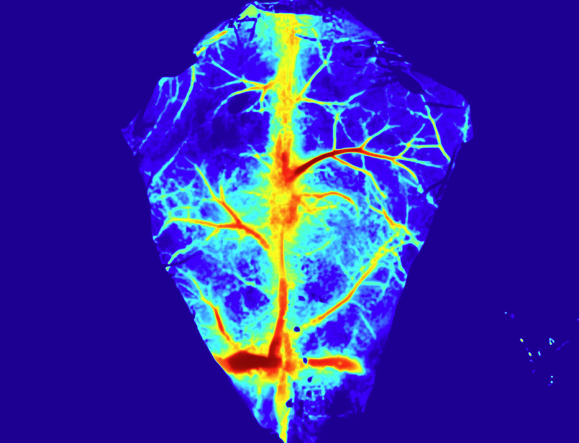

脑卒中模型血流监测

鼠脑缺血再灌注血流成像